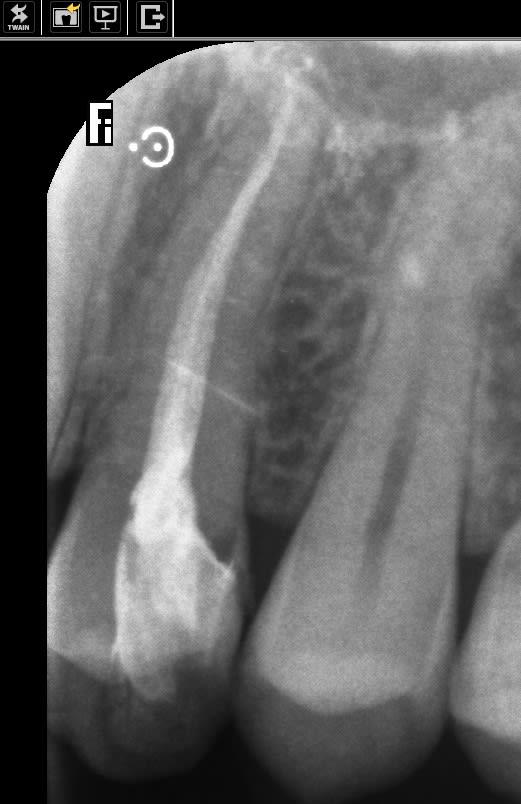

Il y a 2 fonctions dans la longue fraise .

en haut et en bas .

- En haut comme un paralléliseur pour retailler si besoin la face Proxi de la dent d a coté en fonction de ton axe l insertion. alors forcément il faut du grain fin pour mieux polir ensuite

- en bas c est une autre fonction c est pour nettoyer la racine infiltrée et la mettre de dépouille jusqu au fond de la poche .

pourquoi de dépouille ?

pcq il va se faire une attache dessus , mais je ne connais encore jusqu où elle montera mais ce que je sais c est que vais exploiter la partie libre pour la limite de la couronne . Alors tant qu à faire autant ne pas avoir à y retourner pour faire une taille périphérique. Le but étant de juste a avoir a préciser la limite de la prothèse en limite de finition pour le labo .

En gros c est cet axe racinaire qui déterminera l axe de la préparation . Bon pour une couronne ça paraît simple , mais pour un bridge ça prend toute son importance.

Voilà pourquoi c est intéressant d avoir une fraise longue , les 2 actions du haut et du bas étant liées .